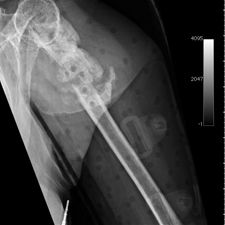

Ms. Q, age 74, initially presented on December 10, 2009, following a multiply comminuted, osteoporotic fracture of her left proximal Humerus. The decision was made to do an ORIF, which was carried out on December 14, 2009. She had a locking plate implanted following which she developed an infection of the wound. She was initially treated with antibiotics for this and she continued to get some oozing of the wound, which did not settle down despite continued use of the various antibiotics including Augmentin. Multiple wound swabs were done which failed to grow any organisms. The oozing persisted until about eight weeks following her operation when it finally settled down and the scar was noted to be tethered and was thought to be tethered onto bone.

She continued to have problems with intermittent cellulitis and pain in the arm and the decision was made to do an early removal of the metal work. This was carried out in mid March 2010 and at operation, which was done through the original incision and anterior extended deltopectoral approach, she was noted to have healed the fracture. She did well postop and was continuing to mobilize.